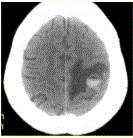

问题 患者女,55岁,右侧肢体无力3d。头颅CT显示如下图。 下一步治疗应首选(提示1周后,患者右侧肢体瘫痪,复查CT如下图。)

选项 A.手术切除 B.继续保守治疗 C.放疗 D.化疗 E.激素治疗 F.抗炎治疗

答案 A